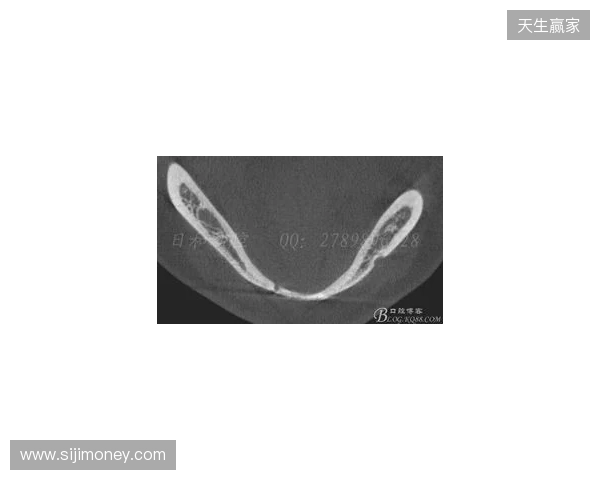

韦林顿确诊上唇部贯通伤;11、21牙半脱位;上颌前牙区牙槽骨骨折

根据医院的检查结果,韦林顿·席尔瓦的上唇部受伤程度较为严重,属于贯通伤,已经进行了清创缝合。这种类型的伤势不仅影响外观,还可能对球员的饮食和发声造成影响。更为严重的是,他的上颌前牙区还出现了骨折,意味着席尔瓦在恢复期间将面临长时间的治疗和康复过程。

球员的第11和第21牙出现了半脱位的情况,这可能会导致他在恢复后需要进行进一步的牙科治疗,甚至有可能影响到他今后的职业生涯。医生表示,虽然通过手术和治疗可以恢复,但心理层面的恢复同样重要。